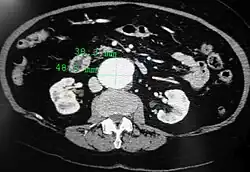

An abdominal aortic aneurysm is usually diagnosed by physical exam, abdominal ultrasound, or CT scan. Plain abdominal radiographs may show the outline of an aneurysm when its walls are calcified. However, the outline will be visible by X-ray in less than half of all aneurysms. Ultrasonography is used to screen for aneurysms and to determine their size if present. Additionally, free peritoneal fluid can be detected. It is non-invasive and sensitive, but the presence of bowel gas or obesity may limit its usefulness.[30] CT scan has nearly 100% sensitivity for an aneurysm and is also useful in preoperative planning, detailing the anatomy and possibility for endovascular repair. In the case of suspected rupture, it can also reliably detect retroperitoneal fluid. Alternative less often used methods for visualization of an aneurysm include MRI and angiography.[31]

Abdominal aortic endoprosthesis, CT scan, original aneurysm marked in blue